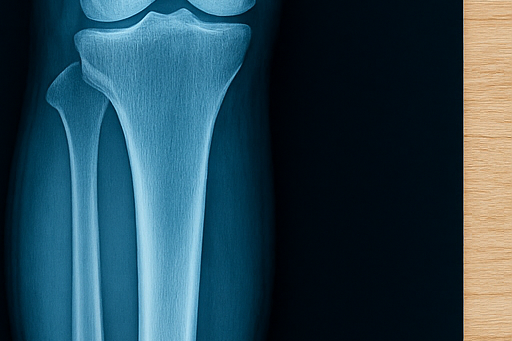

골절은 단순히 뼈가 부러진다는 의미를 넘어, 회복 과정에서 생활 습관과 식습관까지 큰 영향을 받습니다.

특히 피로골절이나 운동 중 발생하는 골절은 치료와 재활에 시간이 오래 걸리기 때문에 음식 선택이 중요합니다.

이번 글에서는 골절 회복에 도움이 되는 음식 10가지와 반드시 피해야 할 음식 5가지를 정리해, 뼈 건강을 빠르게 되찾고 재활 과정에서 놓치기 쉬운 영양 관리까지 함께 살펴보겠습니다.